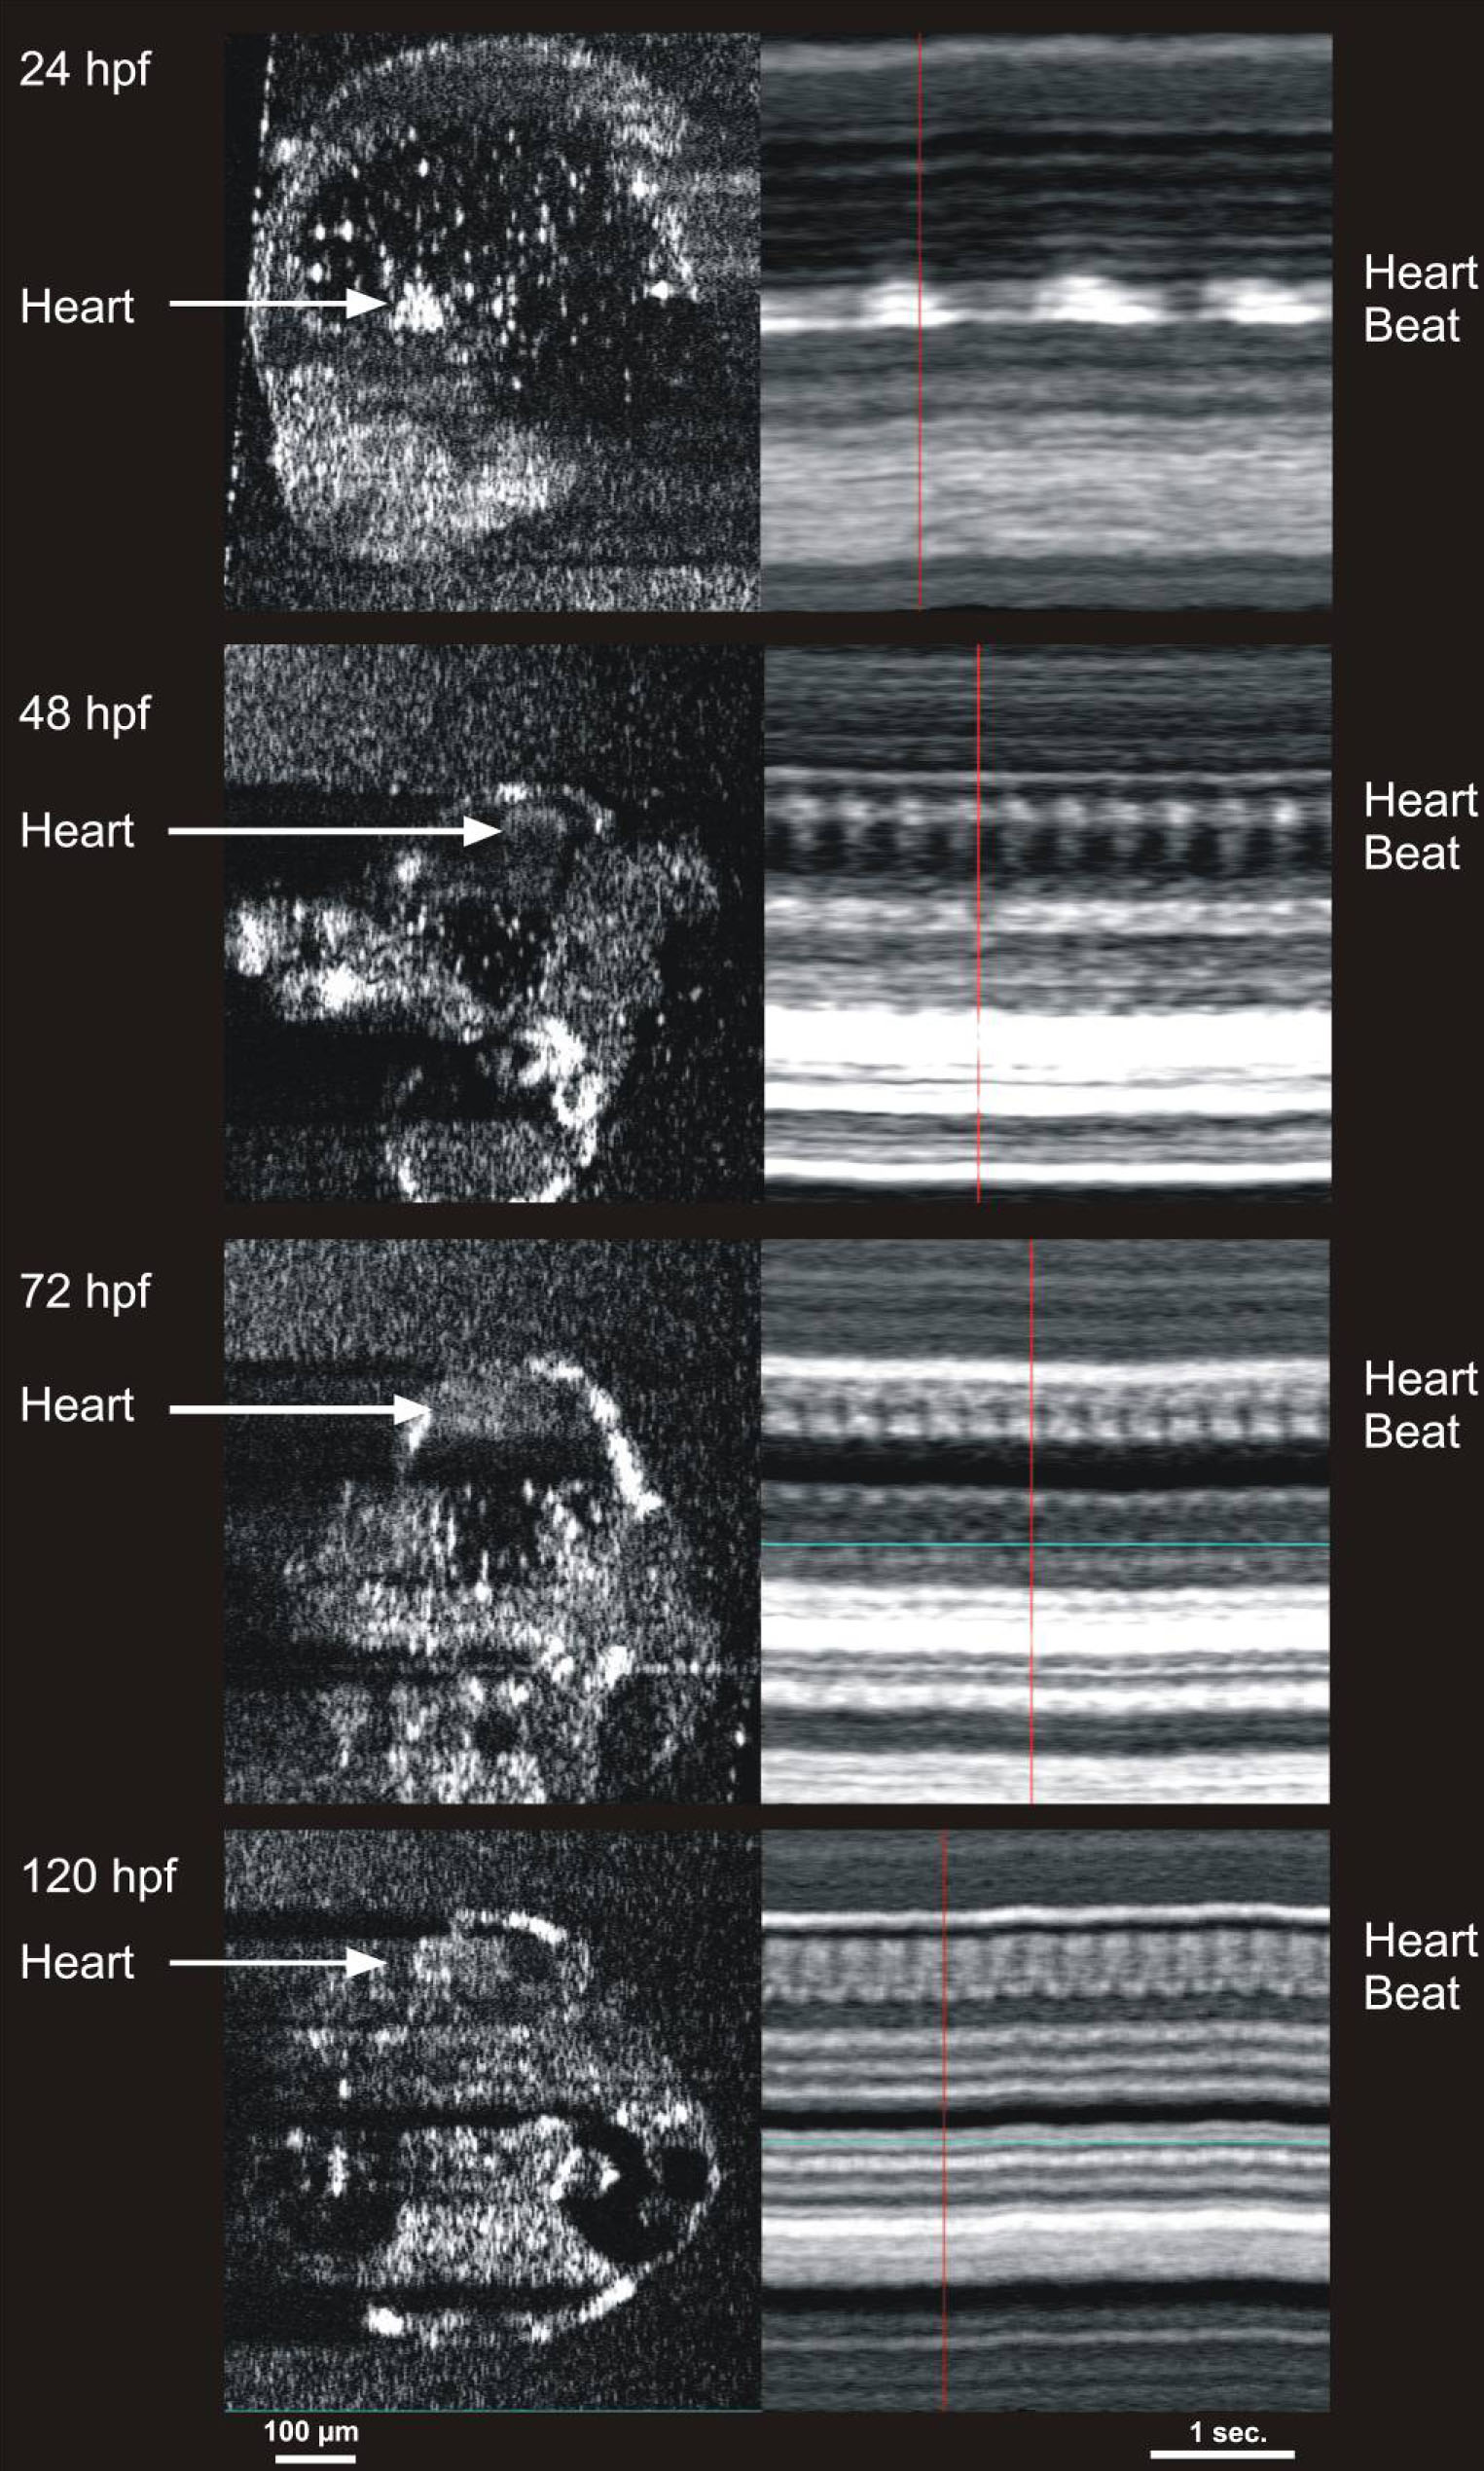

Figure 8. Cardiac M-mode images of the

heart in 24, 48, 72, and 120 hours post fertilization embryos. The

bright signal was created by blood within the heart. Note the increase

in heart rate with development, as well as the development of two

chambers at 72 hours post fertilization (hpf). The heart rates observed

in the m-mode images are 47 beats per min (bpm) in the 24 hpf embryo,

157 bpm in the 48 hpf embryo, 219 bpm in the 72 hpf embryo, and 250 bpm

in the 120 hpf embryo.